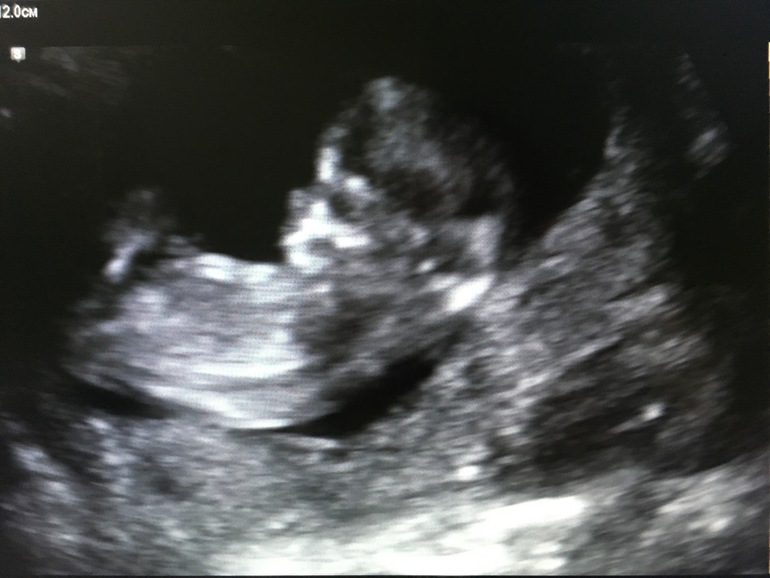

Всем привет) сегодня прошла первый скрининг! Успокоилась)) малыш чувствует себя хорошо! Врач сказала,спокойный ребёночек-не крутился сильно,дал посмотреть все нужные места!))) Сегодня по месячным 13,1 по УЗИ 12,3! Немножко отстаём(овуляция поздняя,цикл длинный). Осталось ещё дождаться результаты крови( ну за них я спокойна,уверена что все хорошо будет)

КТР-5,7

ТВП-1,6

Назальная косточка-2,1

ЧСС-160

Все остальные показатели отличные,органы развиты. Ну и фото нашей Ляли)

Сразу обратила внимание на нос... Папин,большой и курносый🙈